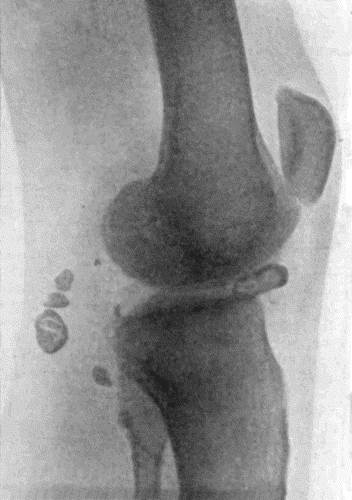

162.Bones of Knee in Charcot's Disease 533

163.Charcot's Disease of Left Knee 534

166.Radiogram of Multiple Loose Bodies in Knee-joint 540

167.Loose Body from Knee-joint 541